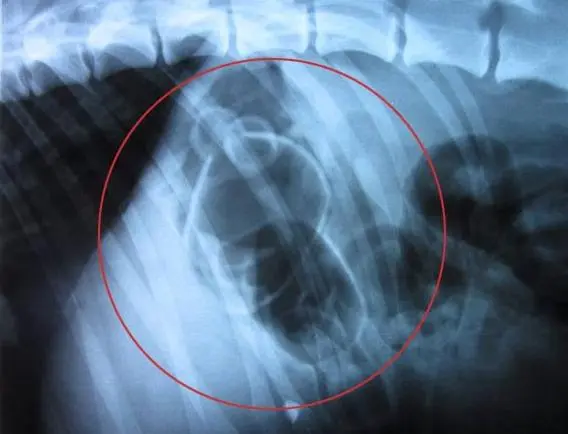

CIRURGIA DELICADA